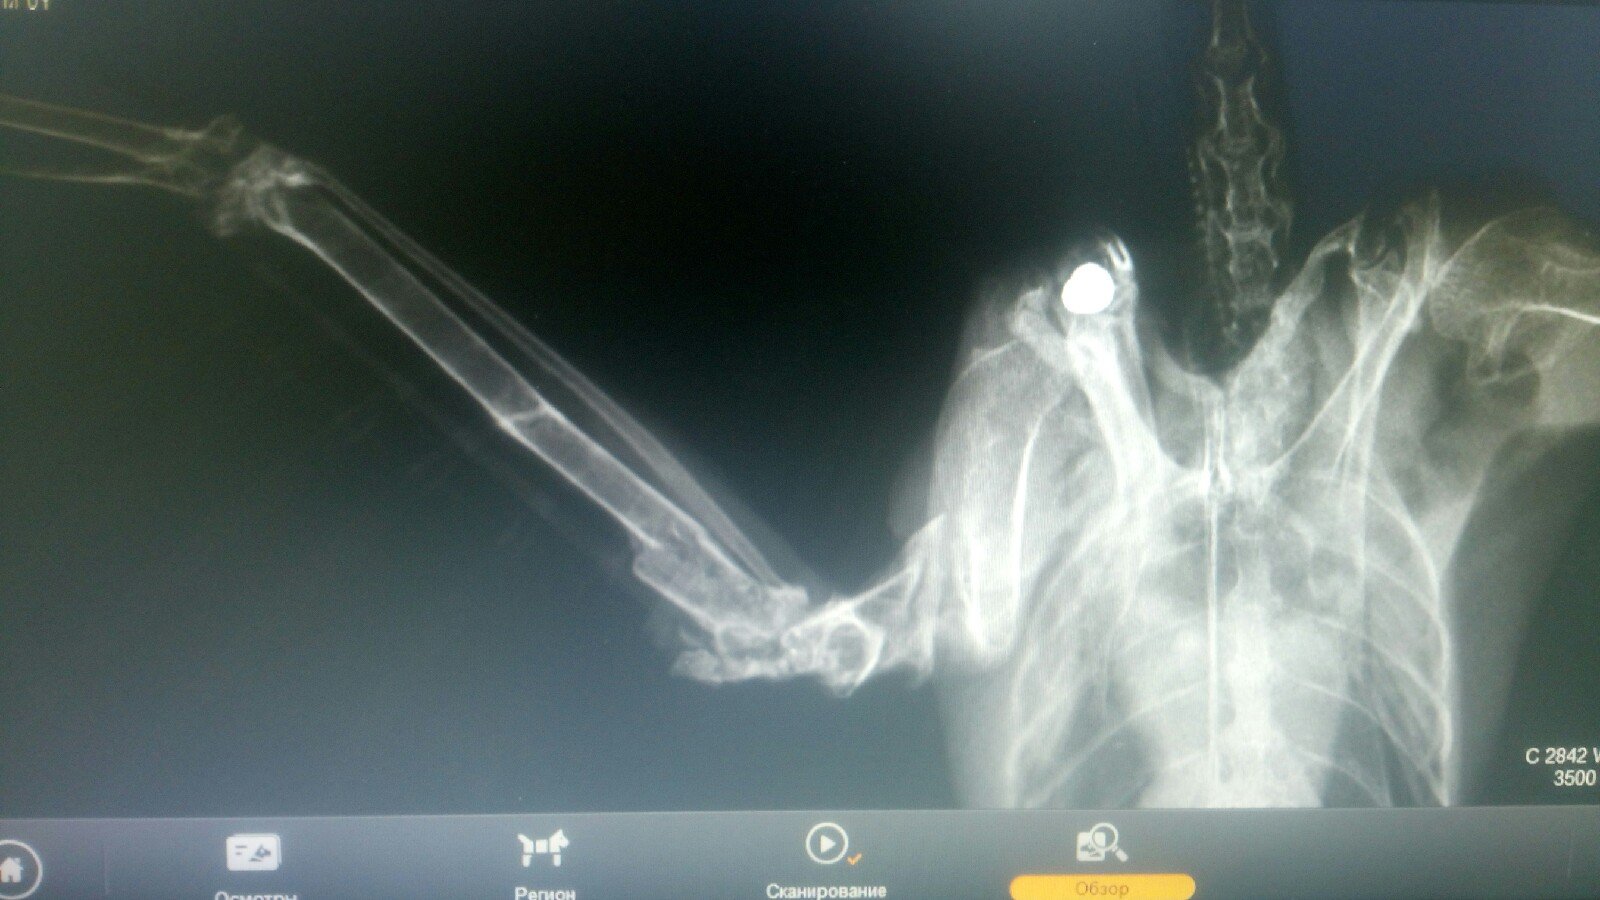

Харлеич Опубликовано 15 февраля, 2019 #1 Опубликовано 15 февраля, 2019 Здравствуйте. Я на форуме новичок, но во вранах немного разбираюсь =) Так как появился новый подстрелыш-переломыш не летный, и не выпускной, то решил что летний маленький вольер больше мне не подходит и нужно делать новый. Спроектировал так, что бы проходил во все нужные мне двери. Врану нравиться. Что скажете, хотел бы услышать конструктивную критику для устранения каких либо недостатков. Сетку использовал с ячейкой 25х25 проволока 1.8. Дерево сосна и ОСБ. Вроде бы постарался избежать всего из за чего может травмироваться птица. внизу планирую дообшить "корыто" линолиумом и насыпать древесного наполнителя без пропитки. Вольер на колесиках, можно катать куда угодно. Купалку уже соорудил, буду ждать когда освоится. При наличии цифрового проекта, строительство вольера заняло около 8 часов, все сводится к напиливанию нужного количества брусков в нужные размеры, зашурупливанию и натяжке сетки. По цене - уложился в 9т.р. ЗЫ. С Враном поработали кроухантеры. В плече пуля и многочисленные переломы, на улице видимо был долгое время все переломы уже срослись. Пуля обросла костной тканью, доставать не стали. Рентген прилагаю. Желающим, могу предоставить проект в формате SolidWorks безвозмездно =)